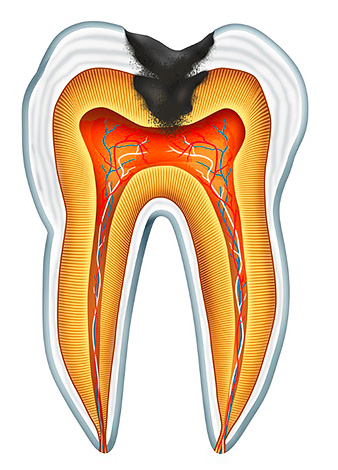

Il processo di necrotizzazione del tessuto polmonare (il cosiddetto "nervo" dentale) nella polpite cancrena cronica è preceduto da uno stadio della sua infiammazione, che è il risultato di una reazione all'azione di alcune sostanze irritanti. Molto spesso, si tratta di batteri e tossine prodotte da loro, che entrano nella polpa attraverso una cavità profonda in presenza di perforazione del fondo e comunicazione con la camera della polpa, o attraverso un sistema di tubi dentinali che passano nello strato dentinale. A volte un'infezione può entrare nella camera pulpare attraverso una tasca parodontale (da sotto le gengive) o entrare nel flusso sanguigno per malattie infettive, ma un tale percorso di infezione retrograda senza carie è estremamente raro.

La polpite gangrenosa cronica è il risultato di acuta diffusa o (meno comunemente) pulite fibrosa cronica. Nella fase acuta dell'infiammazione, vengono attivate le forze immunitarie del corpo e i leucociti escono per combattere l'infezione nella polpa, a seguito della quale c'è edema (aumento delle dimensioni) e formazione di liquidi: prima, sierosa e poi purulenta.

Quindi, sullo sfondo della pulpite acuta diffusa, il "nervo" si disintegra, il che determina con precisione gli attacchi di dolore più gravi, che spesso passano lungo i rami del nervo nell'orecchio, nel tempio, nell'occhio o nella parte posteriore della testa. Non appena si verifica la morte della parte coronale della polpa e l'apertura del fondo della cavità cariata con il rilascio di essudato purulento, si verifica un notevole sollievo: la transizione forma acuta in polmonite cancrenosa.